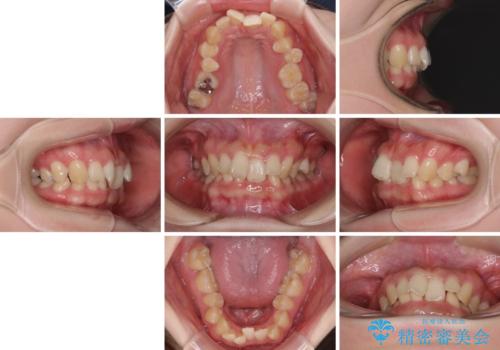

- 全体的な歯列の叢生を気にして来院された患者様です。

奥歯の咬み合わせを見ると、片方は上顎が下顎に対して相対的に前方にあり、他方は交叉した咬合の状態でした。

咬み合わせを改善するためには、上顎臼歯を後方に移動させた咬み合わせにする必要があります。

インビザライン単体で改善することも可能ですが、ディープバイトのためインビザライン単体で達成する可能性が低いと考えられたため、カリエール・ディスタライザーという補助装置を併用して、より確実性を上げることとしました。

カリエール・ディスタライザーを使用している期間、反対側はワイヤー矯正により叢生を解消していくこととしました。

奥歯の咬み合わせを改善しながら、並行してインビザラインで歯列を整えることとしました。